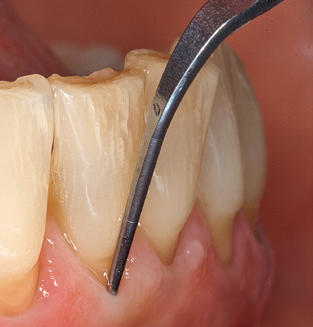

Fig. 4: Flexible probes with millimetre markings are recommended for the probing of dental implants (e.g. Colorvue Kit PCV11KIT6, Hu­Friedy). – Fig. 5a and b: A straight working tip (1P, W&H Dentalwerk Bürmoos GmbH) is a suitable instrument for use on all natural teeth. – Fig. 6: Curved working tips (3Pr/3Pl, W&H Dentalwerk Bürmoos GmbH) lend themselves to the processing of difficult-to-reach areas of the tooth and root surfaces (e.g. furcations). – Fig. 7: The tapered, hexagonal implant cleaning tip (1I, W&H Dentalwerk Bürmoos GmbH) permits atraumatic and efficient cleaning of the crown and abutment surfaces. – Fig. 8: Titanium and carbon curettes are suitable instruments for the manual cleaning of the implant surfaces.

Good illumination of the working field facilitates the process considerably. The system used by the authors achieves this thanks to a 5x LED ring integrated in the handpiece. Naturally, a range of working tips for different indications is also offered. A straight, universally employable tip is the basic instrument required for machine cleaning of natural teeth (Fig. 5a and b). Curved tips, which allow access to exposed furcations, are also available for hard-to-reach areas in the posterior region (Fig. 6).

Following machine cleaning of the tooth and implant surfaces, the surfaces of the natural teeth are cleaned manually using standard hand instruments. When performing manual cleaning, particular attention must be given to maintaining the correct angle of application, appropriate sharpness, good support and working with the curette from apical to coronal. Either titanium or carbon curettes should be used for post-cleaning of the implant structures (Fig. 8). In addition to the use of ultrasonic devices, power jet devices can also be used in conservative dentistry. However, it must be taken into consideration that these procedures are not suitable for removing hard deposits and thus they cannot replace the use of hand instruments and ultrasonic instruments completely. In all cases, cleaning is followed by mechanical polishing of the accessible tooth and implant surfaces with polishing cups and polishing compounds (Fig. 9).